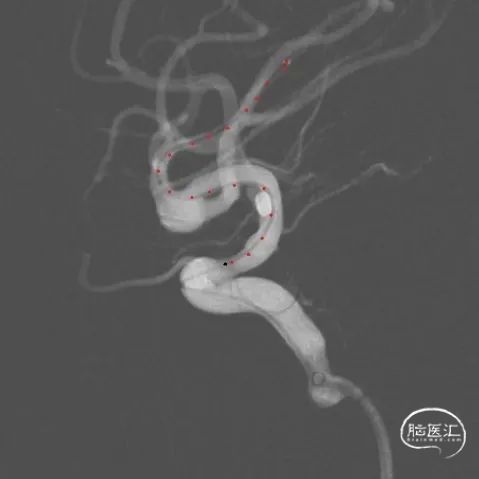

术前三维测量显示瘤体大小,瘤体约8.16mm*3.27mm,累及上下干, 上干约2.43mm,下干约3.56mm。

工作位术前造影及路图。

Synchro10微导丝引导两条SL-10微导管分别超选入右侧大脑中动脉下干(红管)和上干(蓝管)。